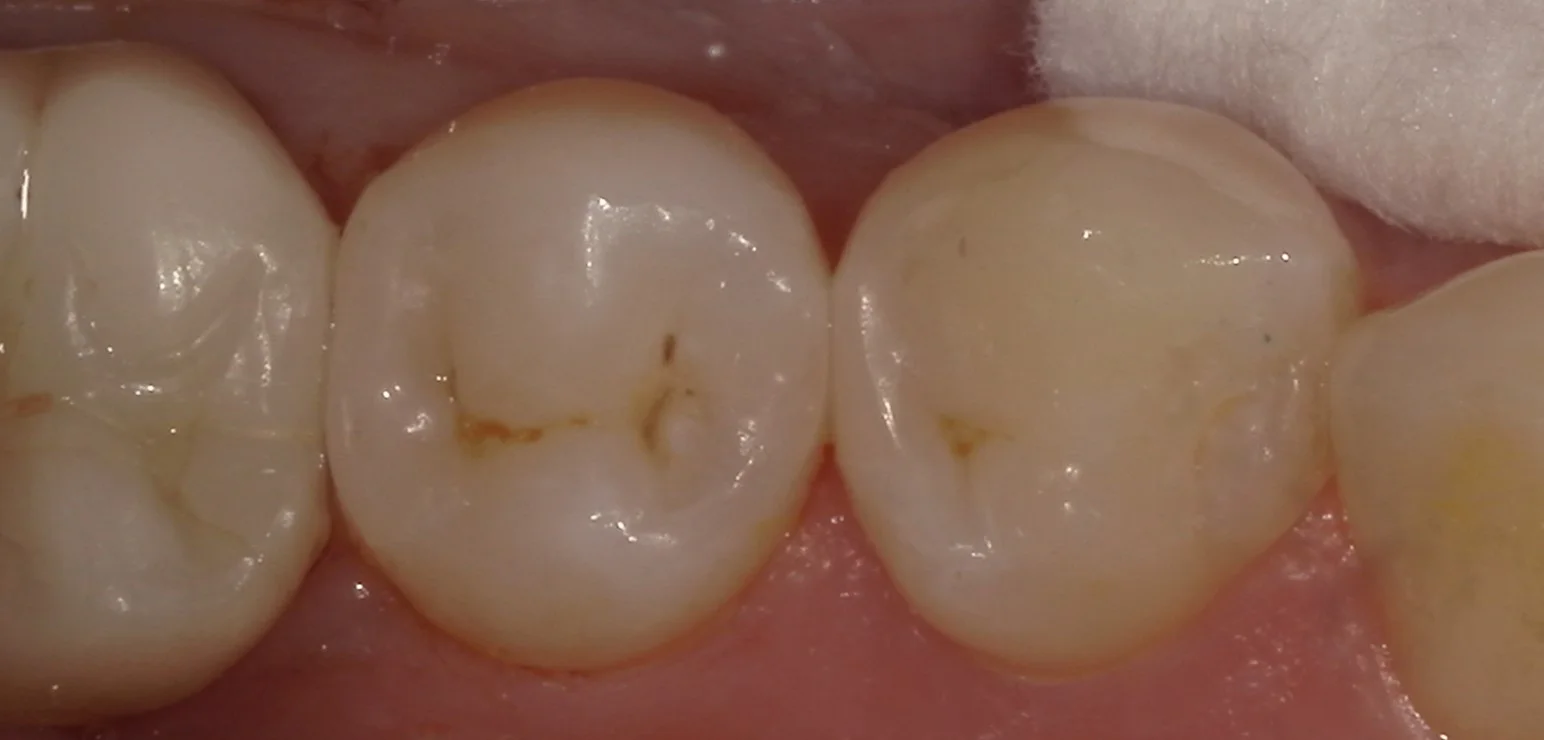

そして詰め終わったのがこちらです。

違和感なく綺麗に仕上げられたかと思います。

最近研磨の手法を切り替えたのですが、ツヤが良く出るようになって更に自然になるようになってきましたね。

術前術後の写真がこちらです。

適合も見栄えも違和感なく綺麗に仕上げられたかと思いますヽ(゚∀゚)ノ パッ☆